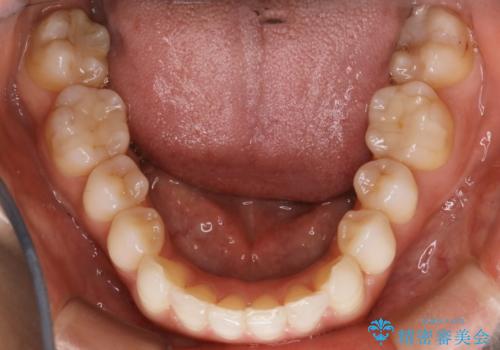

- 嚙み合わせのズレを主訴にご来院されました。

前歯・奥歯ともにセラミッククラウンで治療されている歯があったため、その歯にあまり影響が出ない範囲内で全体の噛み合わせが良くなるような動きを組み込んで治療を進めることとなりました。

矯正治療前にセラミック等の被せ物をされている場合、それ自体の外形は矯正治療では変更することができないため、その他の天然歯の移動に影響を与えてしまう場合があります。また、治療上設定されるアタッチメント(歯の表面に付けるプラスチックの突起)が付かない場合が多く、歯のコントロールが不足する場合があります。